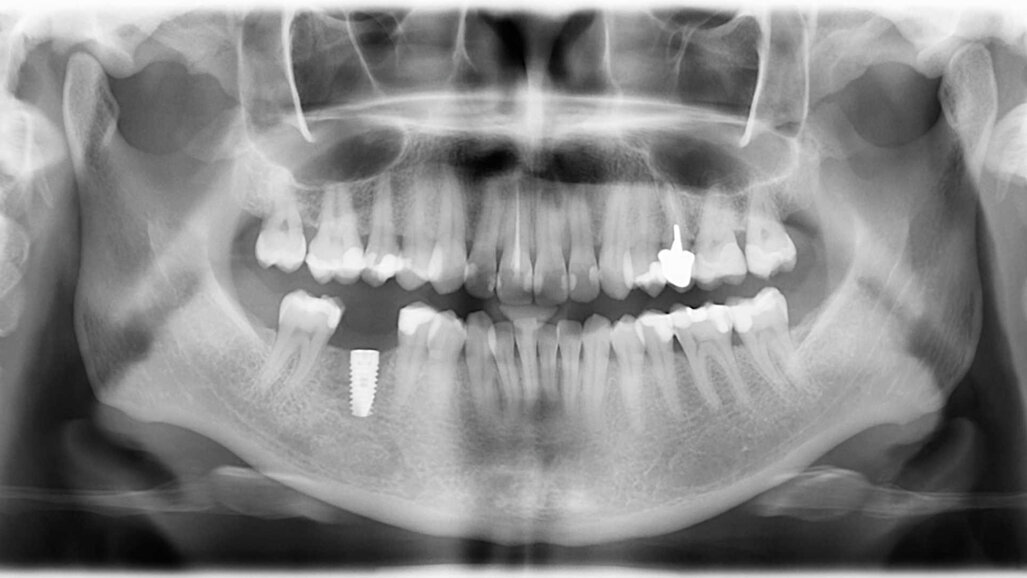

Examen clinique et radiologique L’examen clinique et radiographique met en évidence la possibilité de poser un implant (Figs. 1 et 2).

Fig. 1 : Radio panoramique, on visualise bien le secteur édenté en 46.